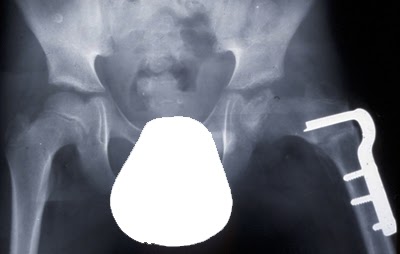

O paciente sofreu uma fratura fechada da diáfise femoral. A

fratura foi tratada com uma haste intramedular fixada com parafusos de bloqueio

distal e proximal.